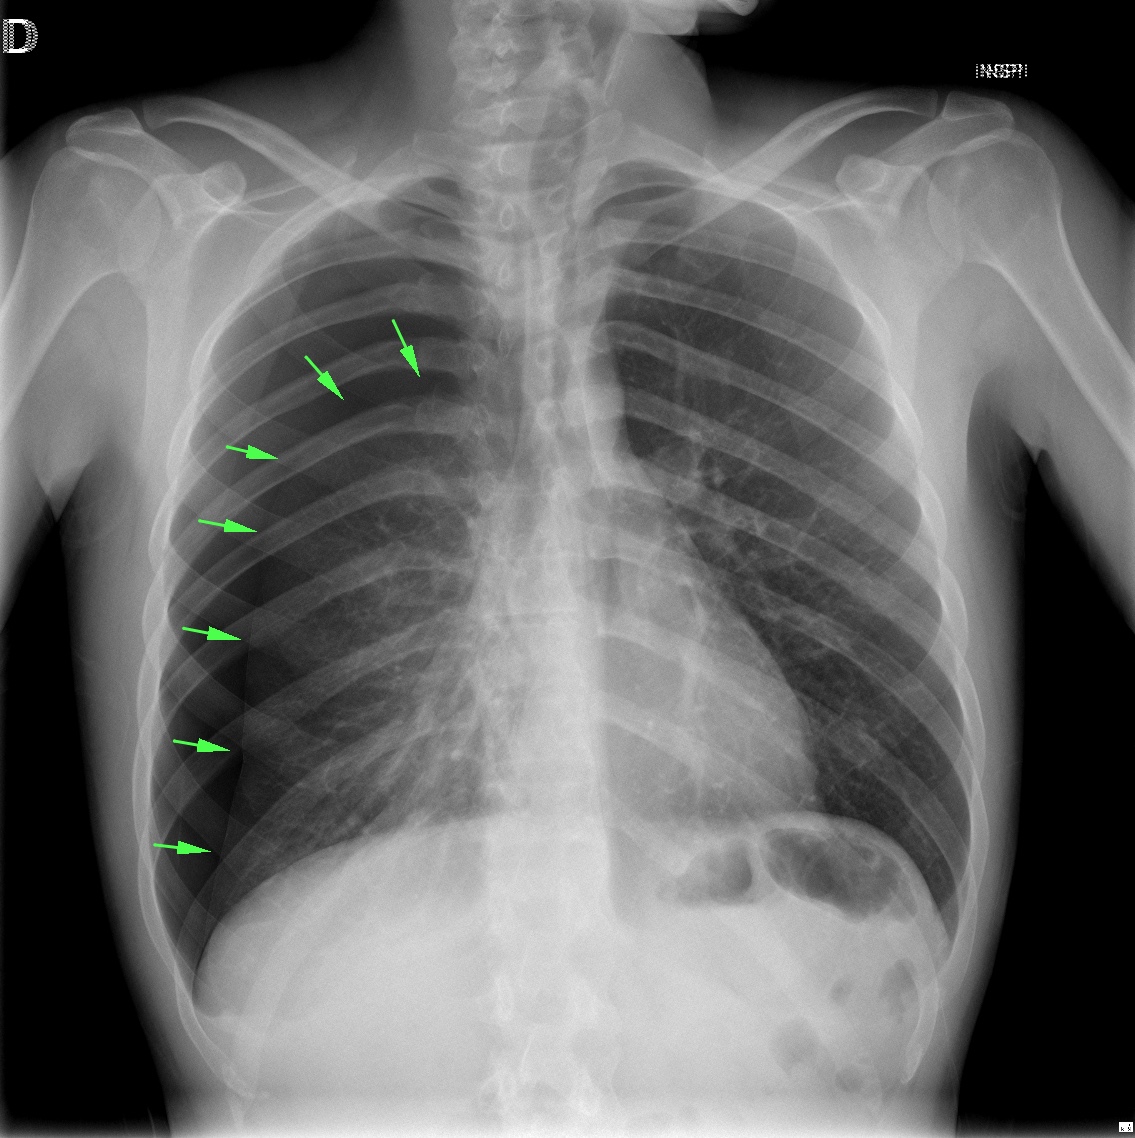

CASO: sospecha de neumonía.

Hallazgos:

- En un principio podríamos decir que existe un aumento de densidad retrocardiaco que podría ser compatible con condensación neumónica a dicho nivel, sin embargo estamos ante una placa poco inspirada, lo cual puede llevarnos a cometer errores diagnósticos.

- Se recomendó volver a realizar la radiografía, observar a continuación:

Ya no se observa el aumento de densidad retrocardiaco, la placa es normal.

INSPIRACIÓN: Una placa bien inspirada es aquella en la que se observar 6-7 arcos costales anteriores o 10-11 arcos costales posteriores. Lo contrario puede producir imágenes falsas de condensaciones o de seudocardiomegalia.